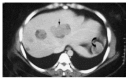

Results: Clinical presentation included a palpable abdominal mass in two patients and vague abdominal discomfort in another two. Two patients were asymptomatic; their tumors were found incidentally on abdominal sonographic examination for other reasons. The final patient was admitted with hemoperitoneum secondary to tumor rupture. The mean diameter of the tumors in the seven patients was 10.5 cm (range 5 to 20 cm). The lesions were located in the body and tail in five cases and in the head of the pancreas in two. Surgical procedures included distal pancreatectomy (3), distal pancreatectomy with splenectomy (2), pancreaticoduodenectomy (1) and a pylorus-preserving Whipple procedure (1). There were gross adhesions or histological evidence of infiltration to the adjacent pancreas and/or splenic capsule in four cases. None of the patients received adjuvant therapy. The mean follow up was 7 years (range 0.5 to 14 years). One patient developed multiple liver metastases after 14 years of follow up.